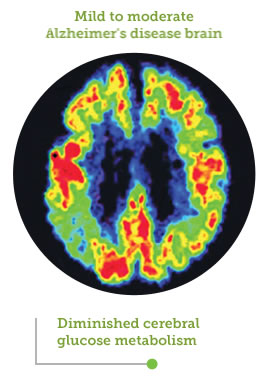

FDG-PET showing areas of cerebral glucose metabolism

Image source: Small GW, Ercoli LM, Silverman DHS, et al. Cerebral metabolic and cognitive decline in persons at genetic risk for Alzheimer’s disease. Proc Natl Acad Sci USA. 2000;97(11):6037-6042. Copyright 2013 National Academy of Sciences, U.S.A.

- DCGM occurs in a characteristic pattern, commonly affecting the posterior cingulate, parietal, temporal, and prefrontal regions of the brain4-10

The brain’s capacity to utilize glucose as fuel is diminished by up to 25%, leaving a large portion of its energy needs unfulfilled1